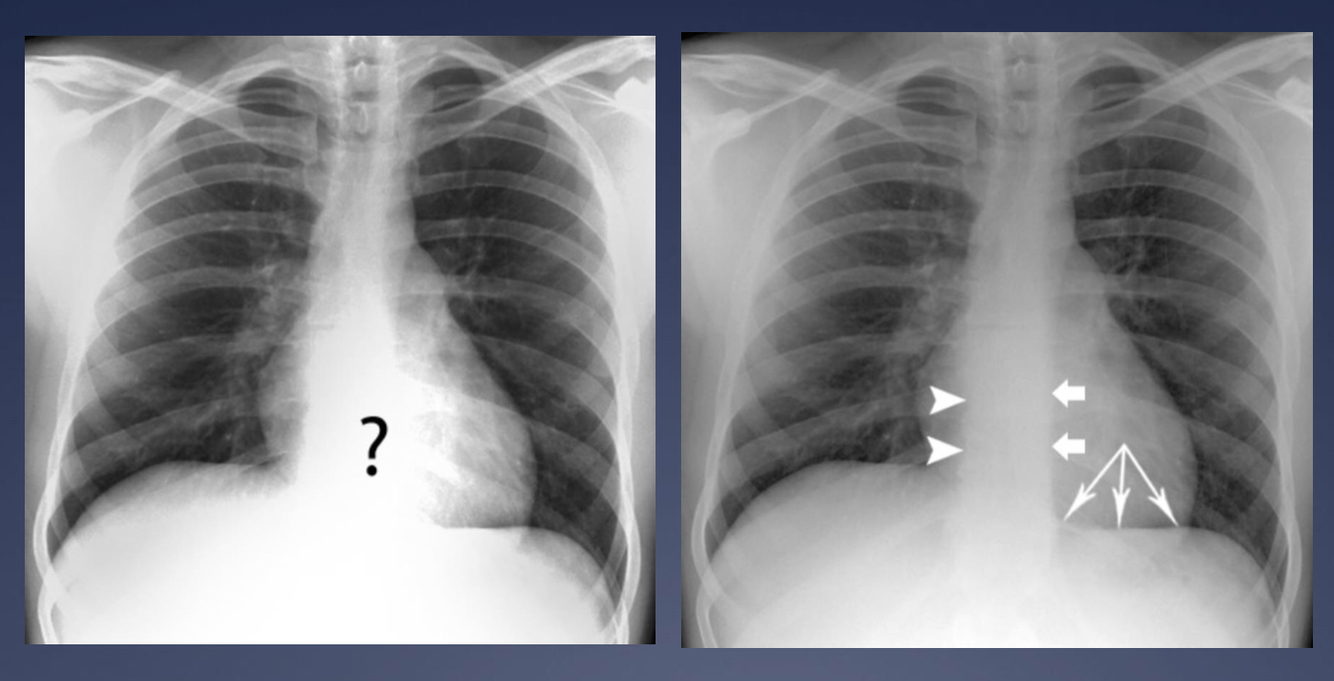

How should we see the diaphragm on an xray?

Running all the way up to the vertebral bodies

What borders of the heart should you see on a chest x ray?

Atrial enlargement carina splays